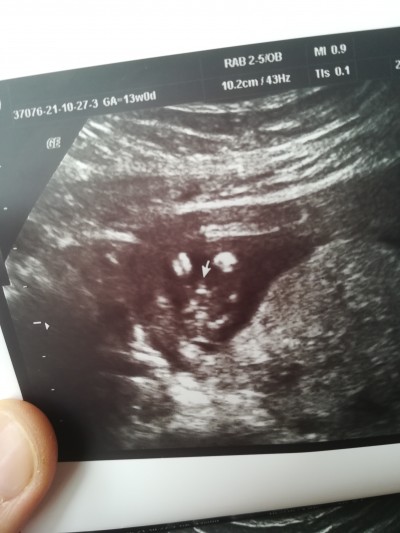

Kızlar 13 haftalık doktora gittim erkek dedi resim verdi ama jprdon olabilirmi acaba

Gebelik haftası 13+1